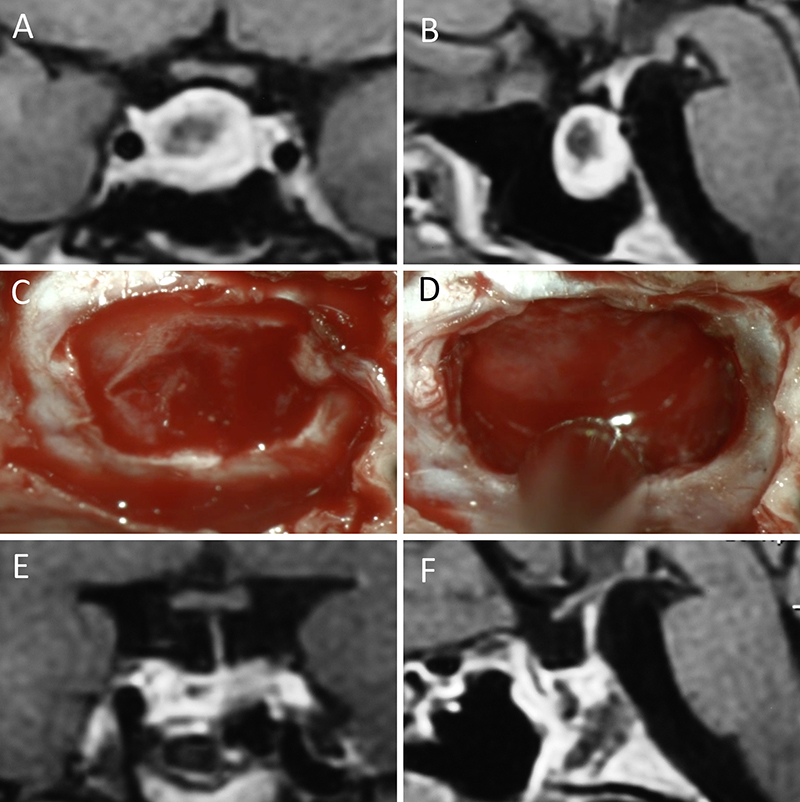

Figura 5: Apoplejía hipofisaria hemorrágica en un hombre de 32 años. El paciente presentó cefalea y parálisis completa del III par. Tuvo restitutio ad integrum en el seguimiento. A-B: RM preoperatoria; C-D: intraoperatorio; E-F: RM postoperatoria.

Figura 6: Apoplejía hipofisaria hemorrágica en un hombre de 55 años. El paciente presentó cefalea, déficit visual y parálisis completa del III par. Evolucionó favorablemente tras la cirugía, revirtiendo el cuadro. A-B: RM preoperatoria; C-D: intraoperatorio; E-F: RM postoperatoria.